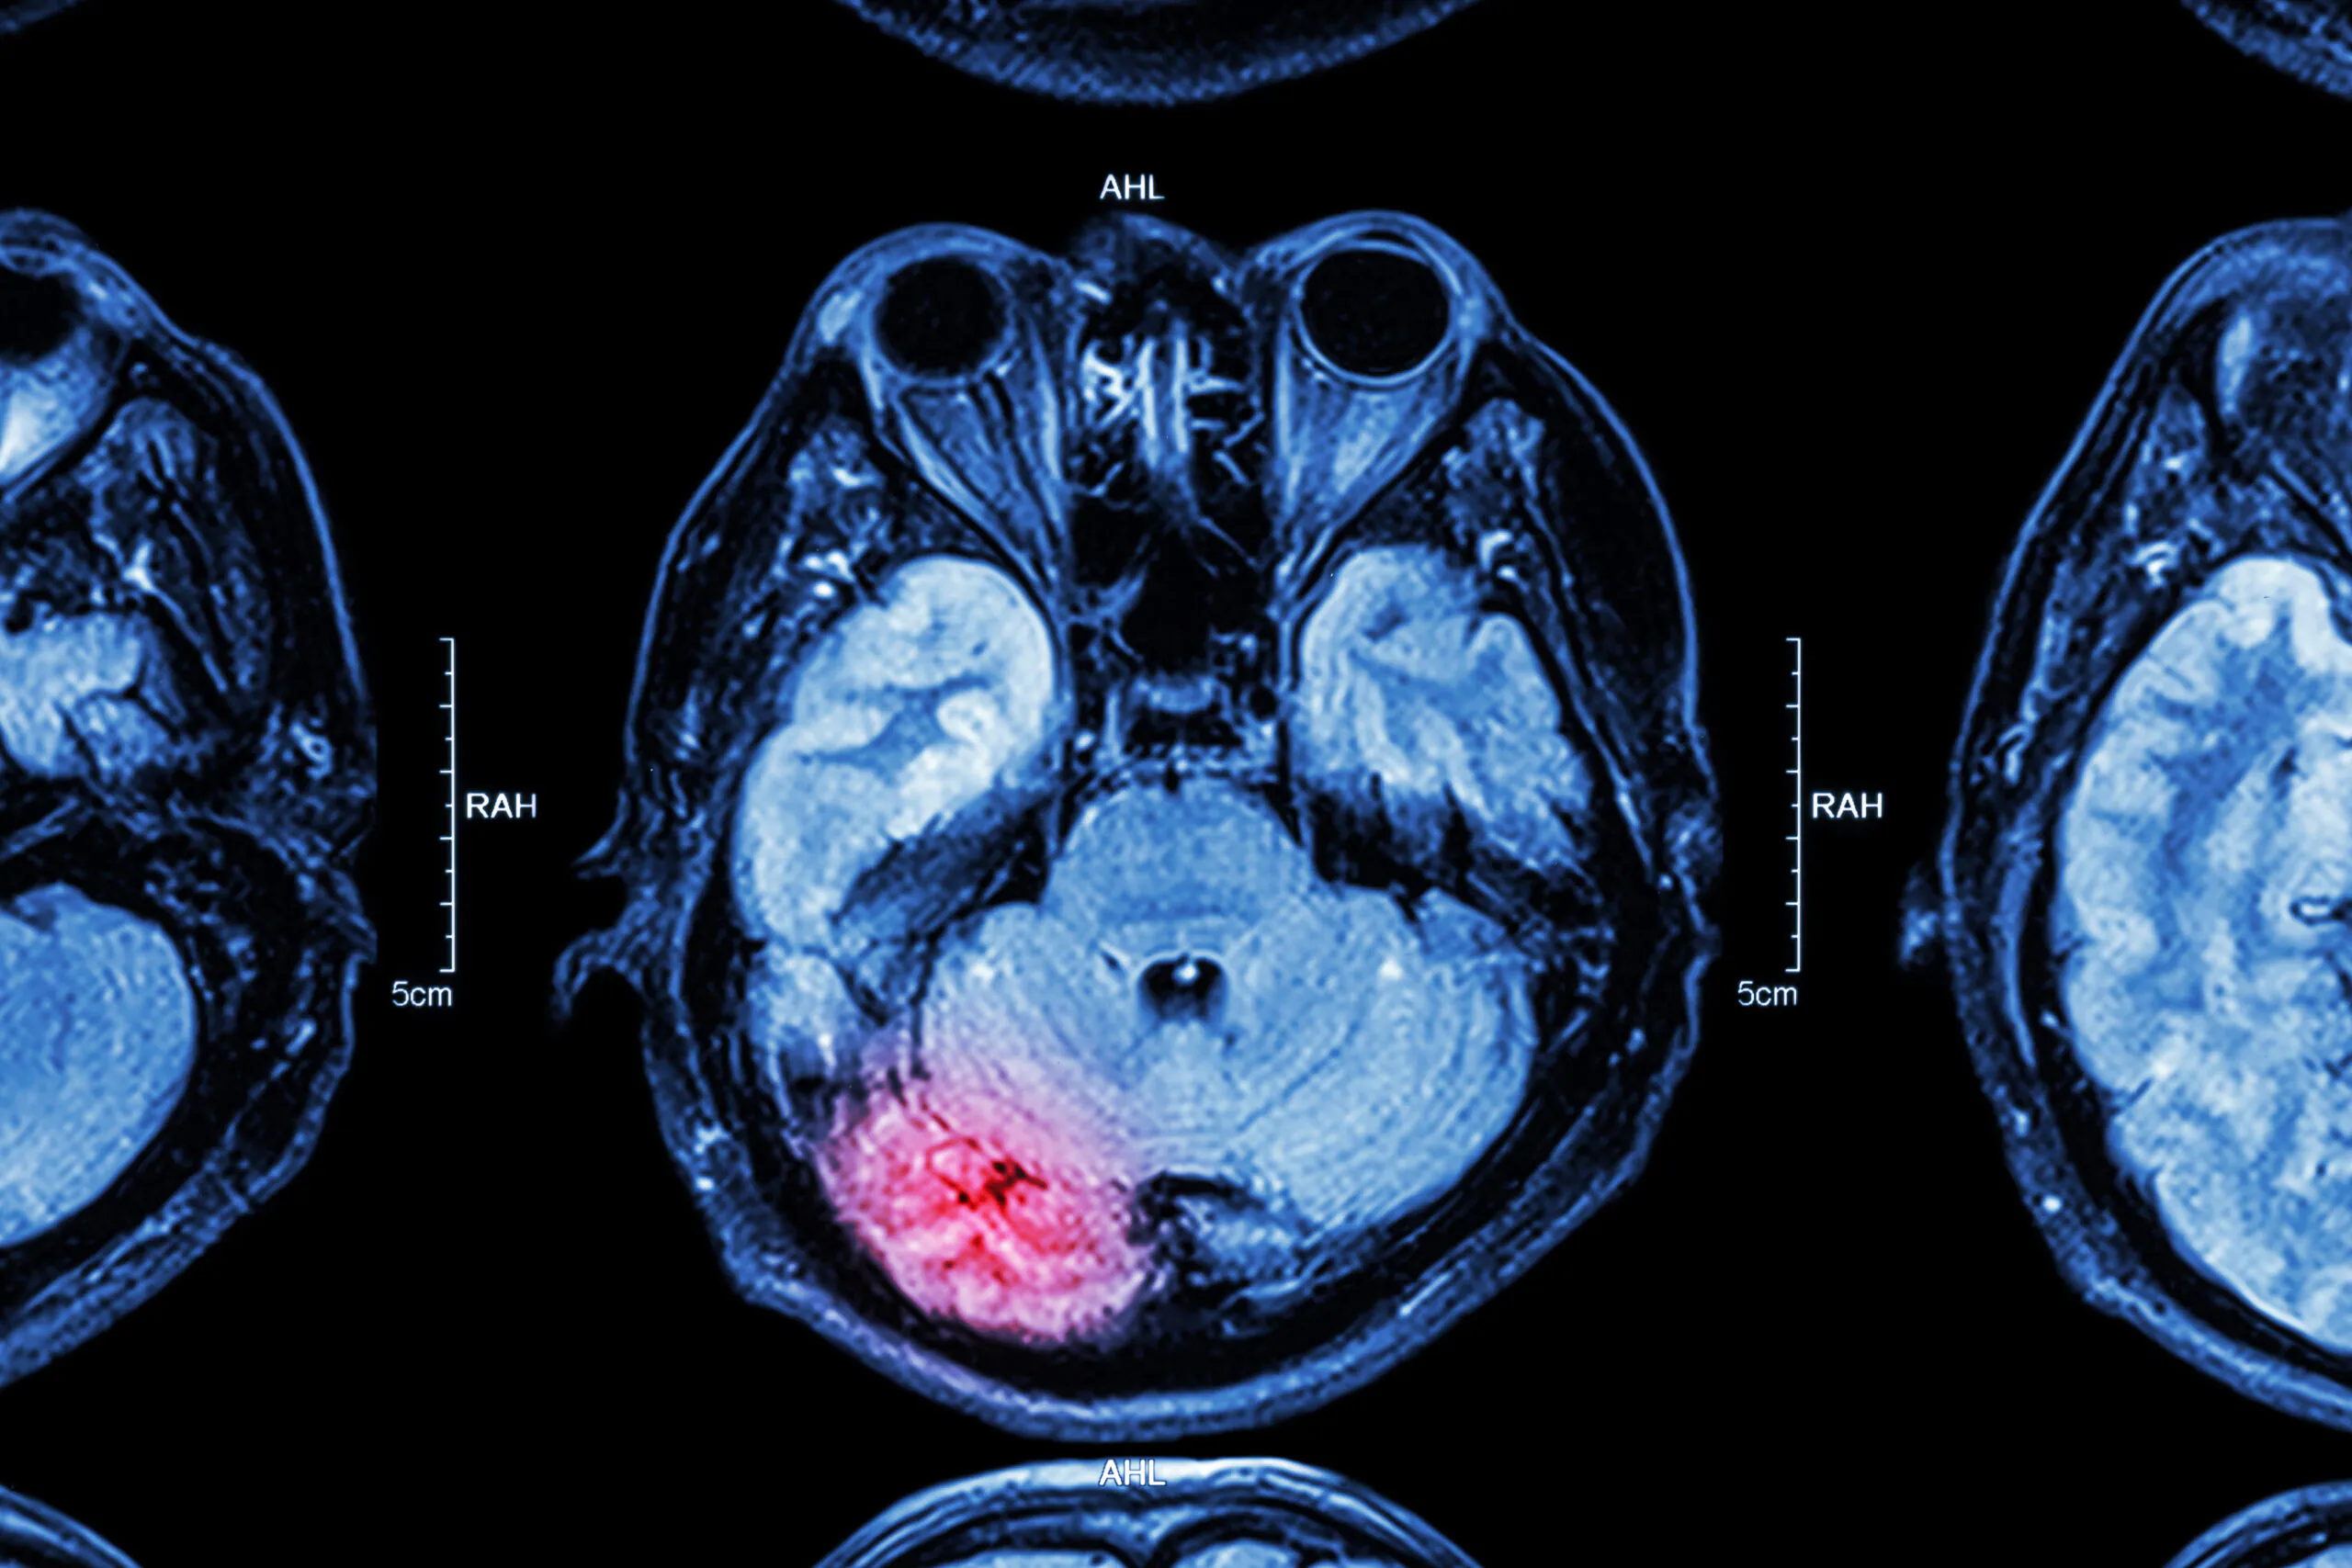

Traumatic brain injuries (TBIs) are among the most devastating and life-altering injuries a person can suffer. These injuries often result in long-term cognitive, physical, and emotional consequences. For victims and their families, the aftermath can be overwhelming—physically, emotionally, and financially.

A traumatic brain injury occurs when the brain sustains damage due to an external force—often from a sudden blow, jolt, or penetration to the skull. TBIs vary in severity from mild (such as concussions) to severe and permanent disabilities.